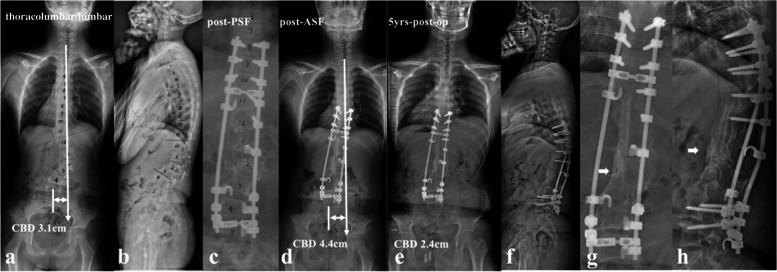

All the recruited patients were stratified according to the location of dystrophic curve apex: thoracic group, 4 cases (26.7%) (Fig. 1a, b); thoracolumbar/lumbar group, 11 cases (73.3%) (Fig. 1c, d). Among them, 1 patient in thoracic group and 3 patients in thoracolumbar/lumbar group received staged surgery with combined posterior-anterior or anterior- posterior approach (Table 1), while the rest 11 patients (73.3%) underwent posterior-only spinal instrumentation and fusion. Supplementary anterior fusion utilizing structural fibular allograft (2 patients) (Figs. 2, 8) or autogenous rib grafts (1 patient) (Fig. 3) was applied when the pedicle screw density in the apical region was distinctively low due to pedicle dystrophy disabling screw insertion. Stage 1 anterior release involving intervertebral disc resection and autogenous rib grafting was performed in 1 patient of thoracolumbar/lumbar group, followed by skull-femoral traction for 2 weeks and subsequent stage 2 posterior spinal correction and fusion.

The present study represented a homogeneous case series of dystrophic NF1 patients with convex trunk shift, and the incidence reached 8.4%. The stratification of distinguishing thoracic from thoracolumbar/lumbar CCI was important, as the incidence of immediate post-op CCI (≥3 cm) was 0.0 and 63.6% for thoracic and thoracolumbar/lumbar groups, respectively. This separation was essential because of its quite different prognosis. The likely mechanism was that the thoracic CCI was usually associated with sufficient distal non-dystrophic pedicles and reliable distal screw purchases to achieve sufficient correction of distal fractional curve and subsequently a horizontal takeoff (Fig. 5). For thoracolumbar/lumbar CCI, limited and unreliable distal screw purchases were inclined to achieve poor correction of lumbosacral fractional curve and subsequently leave residual takeoff angle, increasing the risk of failure of coronal rebalance (Fig. 6).

The quantitative comparative analysis further revealed that in the imbalanced group, a higher correction of main curve Cobb angle is common, resulting in more tilted instrumentation mass, and revers tilt and translation of UIV to the convex side. This is particularly true for thoracolumbar/lumbar CCI with limited distal screw purchases, more residual lumbosacral takeoff angle and easy over correction of upper hemi main curve. Multiple linear regression analysis further revealed that △UIV translation was a key determinant for correction of CCI.

Based on the lessons learned from this rare case series, tips for implementing better correction maneuvers when treating this particular patient group were summarized. Rod insertion with derotation and compression maneuvers firstly on the convex side was well known to be beneficial for correction of main curve. However, over correction was easy to occur with simultaneous reverse tilt and translation of UIV to the convex side, resulting in inadvertent aggravation of CCI, particularly for those with thoracolumbar/lumbar apex and vertical proximal hemi-curve. Contrarily, if the rod was firstly inserted on the concave side using translation rather than derotation and cantilever as main correction technique, the risk of over correction of main curve was relatively small, reducing the risk of CCI aggravation. The position of UIV, being represented by its tilt and translation, was of valuable information in evaluating whether or not the coronal rebalance failed intraoperatively. If the UIV tilt and translate to convex side, fine-tuning using concave compression/convex distraction and coronal rod bending in upper hemi-curve region were beneficial to increase the coronal compensation (Fig. 7). Finally, a vertical morphology of instrumentation being confirmed by intraoperative fluoroscopy was essential for reliable coronal realignment.

The follow-up data revealed that patients in the imbalanced group experienced spontaneous improvement of CCI over time (Ratio of CBD < 3 cm: 100%). This usually resulted in an acceptable but not satisfying coronal alignment because residual tilting of the instrumentation mass and/or junctional angulation centering around LIV existed (Fig. 8), and might result in implant failure (Fig. 5). Both distal compensation (decreased tilting of the instrumentation mass and LIV to the convex side) and proximal compensation (increased UIV disc angle) accounted for such coronal rebalance, and our data was suggestive that the distal compensation was the mainstay compensative mechanism. This was in line with Bao’s previous finding that LIV at L4 or higher was correlated to a higher chance of spontaneous coronal rebalance [ref. 7].